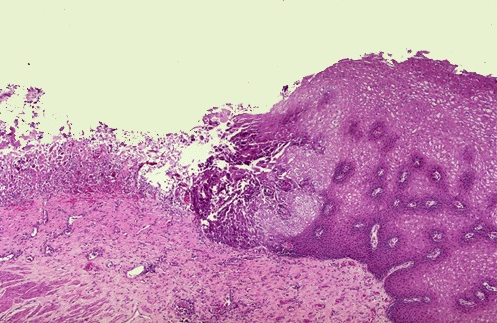

Corresponde a un patrón inflamatorio agudo ulceroso.

100%

0%